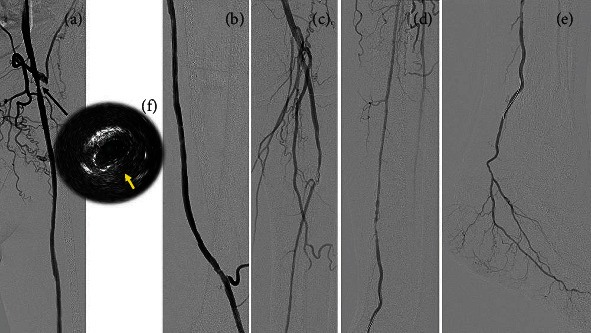

背景:先前的报道已经揭示了人工股腘动脉旁路闭塞(PFPBO)的各种血管内介入技术;然而,对于大多数介入医师和血管外科医生来说,PFPBO的治疗仍然具有挑战性,因为手术过程复杂。大多数报道的技术涉及装置植入。在本研究中,我们在不植入任何额外装置的情况下,对PFPBO进行了外科移植取栓和药物包被球囊血管成形术的联合治疗。此外,我们通过随访血管造影确定了这种治疗的良好长期结果。案例演示。一名77岁男性,有慢性肾脏疾病和冠状动脉疾病病史,左腿静止疼痛。在本次会诊的七年前,由于支架内左股浅动脉(SFA)闭塞,他接受了股腘动脉搭桥(fbp)手术。术后四年,超声扫描显示近端吻合口狭窄;因此,继续进行药物治疗。在目前的咨询中,诊断性血管造影显示FPB和髌下血管闭塞。在第一次再通的尝试中,导丝无法通过阻塞的SFA。因此,采用另一种技术来重建FPBO和腘窝下血管。我们通过右股总动脉(CFA)插入引导鞘后进行了左腿血管造影。首先,通过暴露的左侧CFA使用Fogarty导管进行手术取栓。在通过右侧CFA进行血管内治疗后,我们对吻合口狭窄和闭塞的腘下血管进行了药物包被球囊血管成形术。随访血管造影未见再狭窄。在进一步的随访血管造影中,义肢近端吻合口残余狭窄明显消退。结论:这种新的血运重建策略可能是治疗PFPBO的一种可行的选择。

Background: Previous reports have revealed various endovascular intervention techniques for prosthetic femoropopliteal bypass occlusion (PFPBO); however, treatment for PFPBO remains challenging for most interventionalists and vascular surgeons because the procedure is complicated. Most of the reported techniques involve device implantation. In the present study, we performed a combination of surgical graft thrombectomy and drug-coated balloon angioplasty for PFPBO without implanting any additional devices. Furthermore, we determined the favorable long-term results of this treatment using follow-up angiography. Case Presentation. A 77-year-old man with a history of chronic kidney disease and coronary artery disease presented to our clinic with rest pain on his left leg. Seven years prior to the current consult, he underwent femoropopliteal bypass (FPB) surgery using a prosthetic graft due to in-stent occlusion of the left superficial femoral artery (SFA). Four years after surgery, a duplex ultrasound scan revealed stenosis of the proximal anastomosis site; hence, medical therapy was continued. On the current consult, diagnostic angiography revealed occlusion of the FPB and infrapopliteal vessels. In the first attempt at recanalization, the guidewire was unable to pass through the occluded SFA. Therefore, another technique was performed to revascularize the FPBO and infrapopliteal vessels. We obtained an angiography of the left leg after inserting the guiding sheath via the right common femoral artery (CFA). First, surgical thrombectomy using a Fogarty catheter via the exposed left CFA was performed. Following endovascular therapy via the right CFA, we performed drug-coated balloon angioplasty for anastomotic stenosis and recanalized occlusive infrapopliteal vessels. Restenosis was not observed on follow-up angiograms. On further follow-up angiography, there was notable regression of the residual stenosis at the proximal anastomosis of the prosthetic graft.